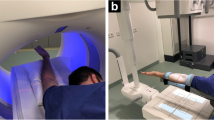

Flat-panel CT (FPCT) and MR arthrography data acquisition

Shoulder joints were injected in the rotator interval under fluoroscopic guidance according to a standardized procedure using 1 ml of local anaesthetic, followed by a mixture of 3 ml of iodinated contrast agent (iopromide, Ultravist 300 mg iodine/ml Bayer Healthcare, Berlin, Germany) and 5 ml of gadolinium contrast agent (gadoteric acid, Artirem 0.0025 mmol gadolinium/ml, Guerbet Group, Villepinte, France). Hence, concentration of iodine in the injected solution was 100 mg iodine/ml leading to an expected intra-articular concentration of about 80 mg iodine/ml according to previous studies [8, 14]. Although iodine may impact on the SNR of gadolinium-enhanced MR arthrography, the effect may be negligible at an intra-articular iodine concentration of 80 mg iodine/ml [20]. Both fluoroscopy and FPCT acquisitions were performed on the same unit (Artis zeego, Siemens Healthcare, Forchheim, Germany) using equal acquisition parameters as used in the in vitro acquisitions (Fig. 1).

Twenty-nine-year-old male patient lying supine on the examination table of the roboter arm mounted C-arm flat panel CT (FPCT) unit with the right shoulder in the isocentre of the eccentric C-arm rotation trajectory (a). After fluoroscopically guided contrast injection (b) FPCT 20-s arthrography of the right shoulder was performed in the same unit (c, coronal reformat). Patient underwent MR arthrography of the same shoulder joint immediately after FPCT (d, T1-weighted fat saturated (FS) coronal image). Normal glenohumeral joint with intact supraspinate tendon is visualized in both modalities

Following contrast injection, all patients underwent MR arthrography at 1.5 T (Signa EXCITE HDx, GE Healthcare, Waukesha, WI, USA) of the affected shoulder within a maximum of 30 min using a dedicated 8-channel shoulder coil (Neocoil, Pewaukee, WI, USA) and the standard MR acquisition protocol of our institution (Supplemental Table 1).